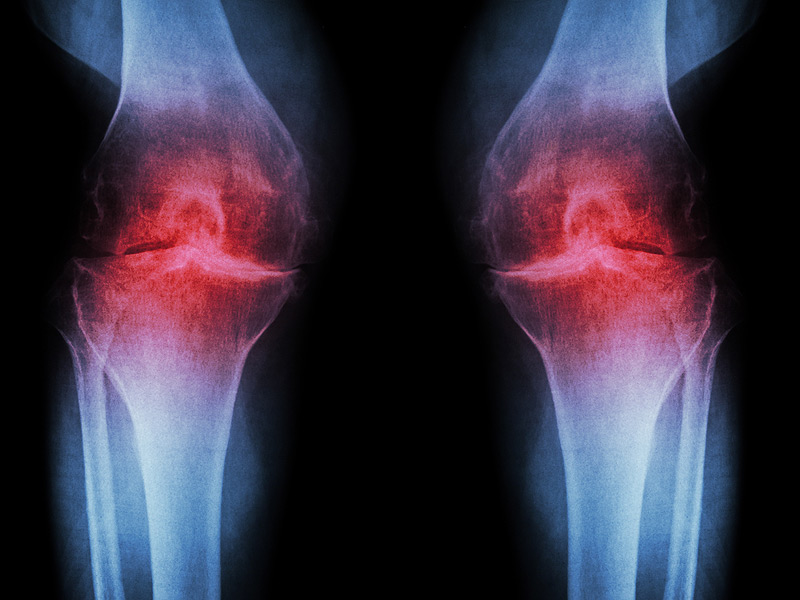

বাংলায় যাকে আমরা হাঁটু বাথা বলি সাধারণত মেডিক্যাল এর ভাষায় একে অষ্টিওআর্থাইটিস বলা হয়, আপনি একে সহজভাবে বয়সজনিত হাঁটু ক্ষয়ও বলতে পারেন।

এটি সাধারণত ৪০ বছর বয়স থেকে শুরু হয় আর চলতে থাকে জীবনের শেষ দিন পর্যন্ত যদি না আপনি একে সঠিক চিকিৎসার মাধ্যমে নিয়ন্ত্রণে না রাখেন।